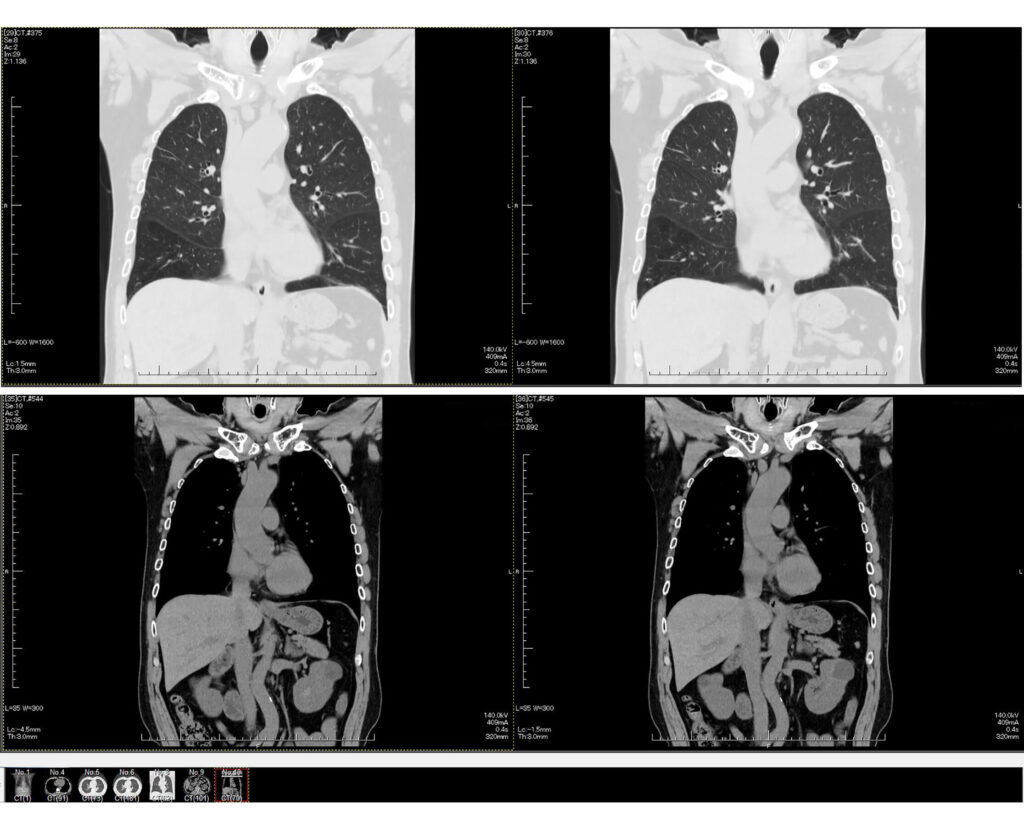

DWIBS検査は主に頚部から骨盤までの広い範囲を一度に撮影できるMRI技術の一つです。「Diffusion-weighted Whole body Imaging with Background body Signal」の略としてDWIBS(ドゥイブス)と呼ばれています。

全身の悪性腫瘍を短時間で描出できることから、がんの早期発見や治療経過の観察などで注目されています。検査自体は30分程度で終了し、検査台で横になっているだけで完了します。検査前後の特別な処置や準備は不要で、体への負担も少ないのが特徴です。

DWIBS検査は、食道・肺・大腸・膵臓・肝臓・胆嚢・乳房・悪性リンパ腫・前立腺・腎臓・尿管・膀胱などのがんを描出することに長けています。

同じく全身がん検査であるPET-CT検査と比べると、前立腺・腎臓・尿管・膀胱などの腫瘍に対して特に精度が優れているのも特徴です。